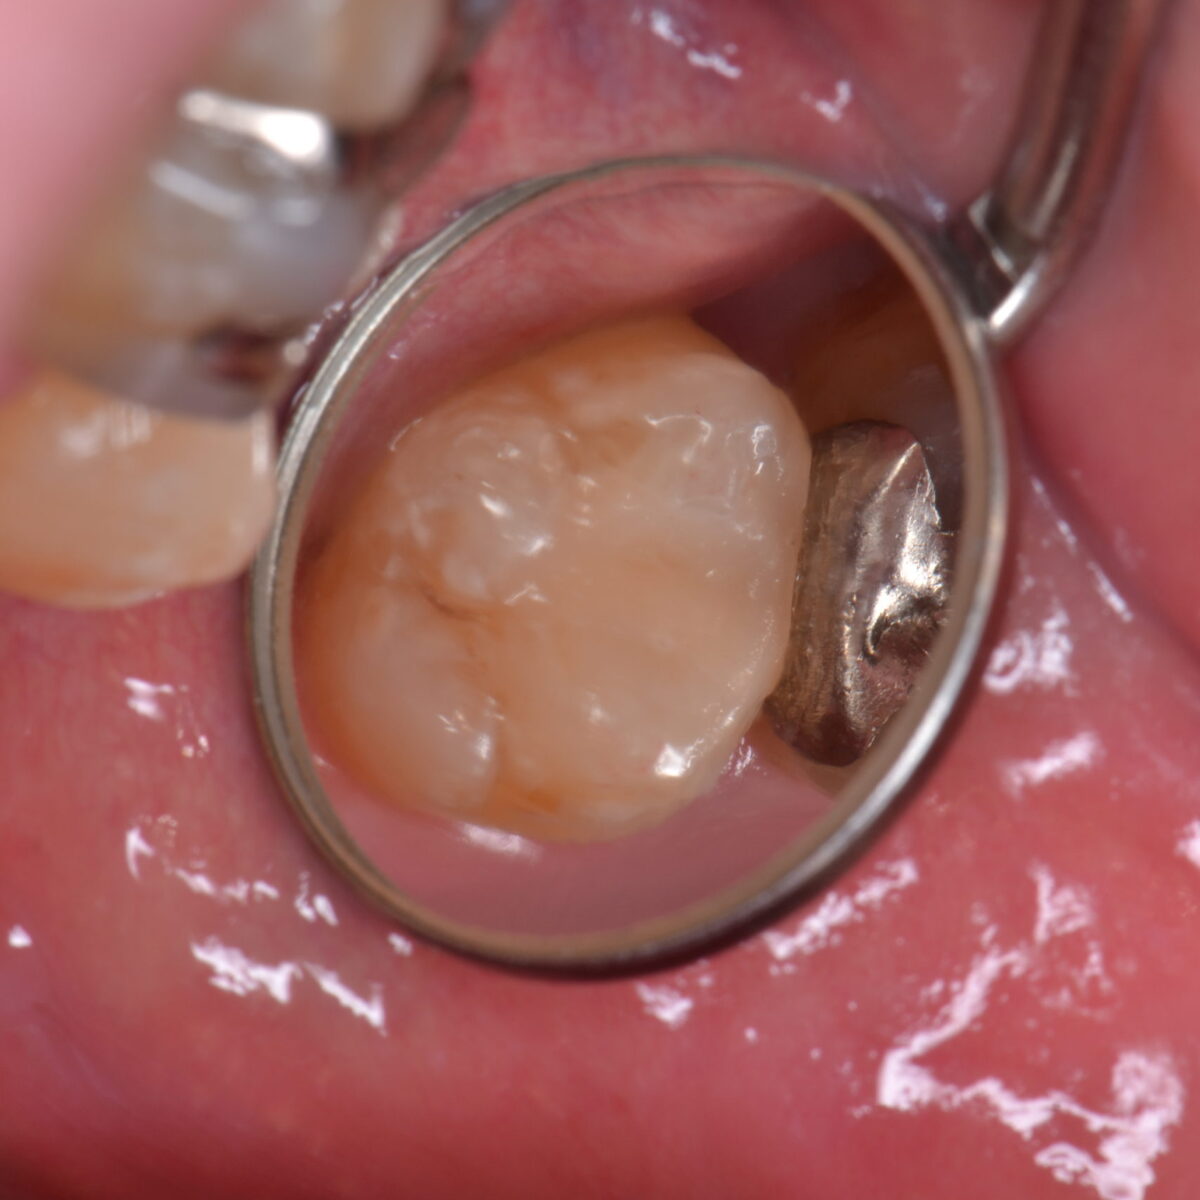

奥歯の白いつめもの

市川、妙典の歯科医院、めぐりデンタルクリニックの梶原です。 本日は奥歯の治療について写真をのせます。 奥歯の歯と歯の間の虫歯です。食べ物が詰まっているのが見えると思います。 削ると…